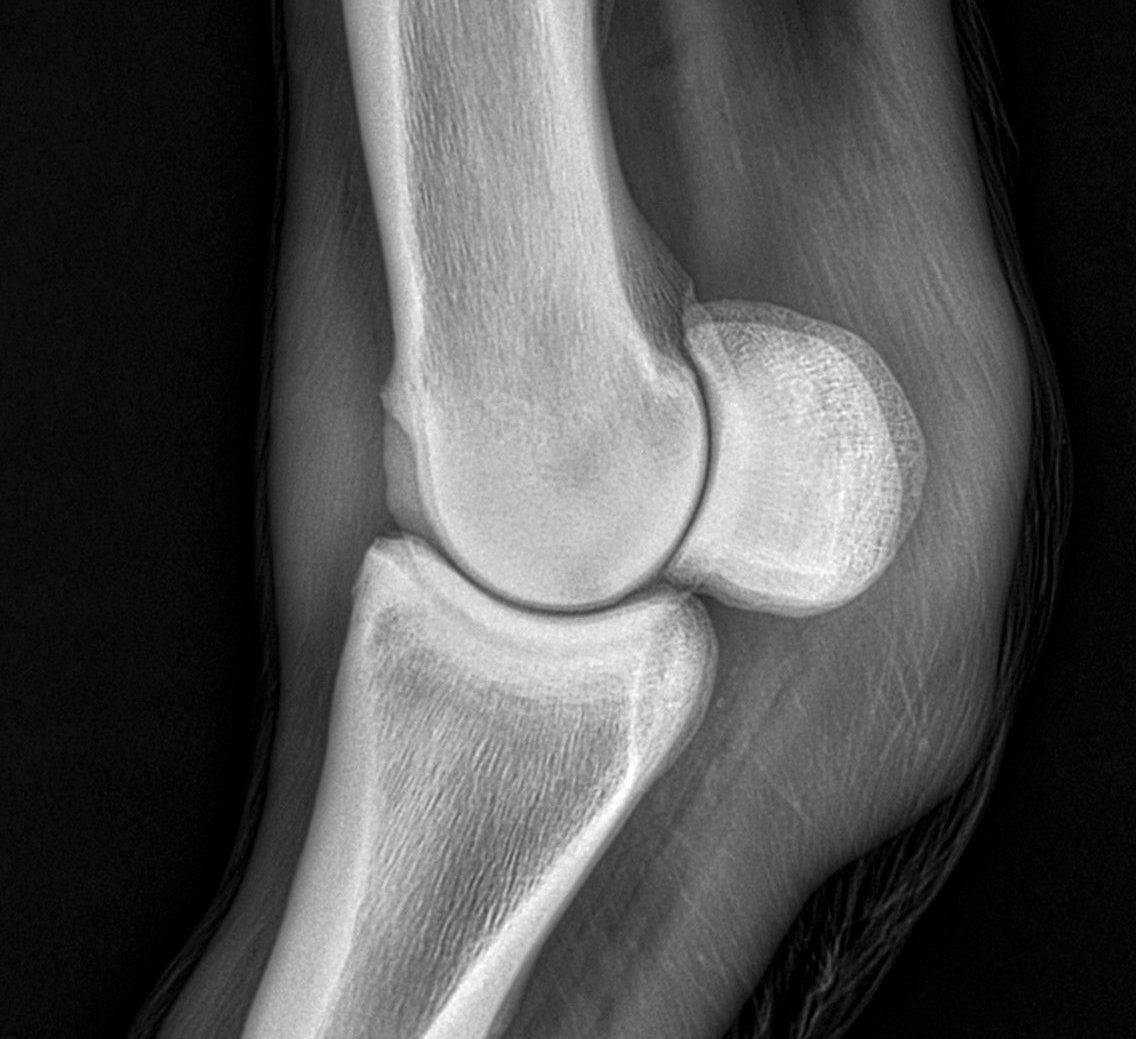

- Digitales Röntgen: Radiologische Untersuchungen stellen in der Orthopädie ein unabdingbares Diagnostikum dar und werden vor allem zur Detektion von knöchernen Veränderungen eingesetzt. Im Rahmen der Lahmheitsuntersuchung können insbesondere die

Gliedmaßen, die Hals-, Brust- und Lendenwirbelsäule sowie Teile des Schädels röntgenologisch auf mögliche pathologische Veränderungen untersucht werden. - Sonographie: Die ultrasonographische Untersuchung (Ultraschall) ist das Standarddiagnostikum für Erkrankungen im Weichteilbereich, wie z.B.: